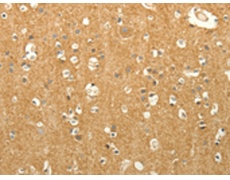

IHC positive control: |

Human brain and Human liver cancer |

IHC Recommend dilution: |

50-200 |